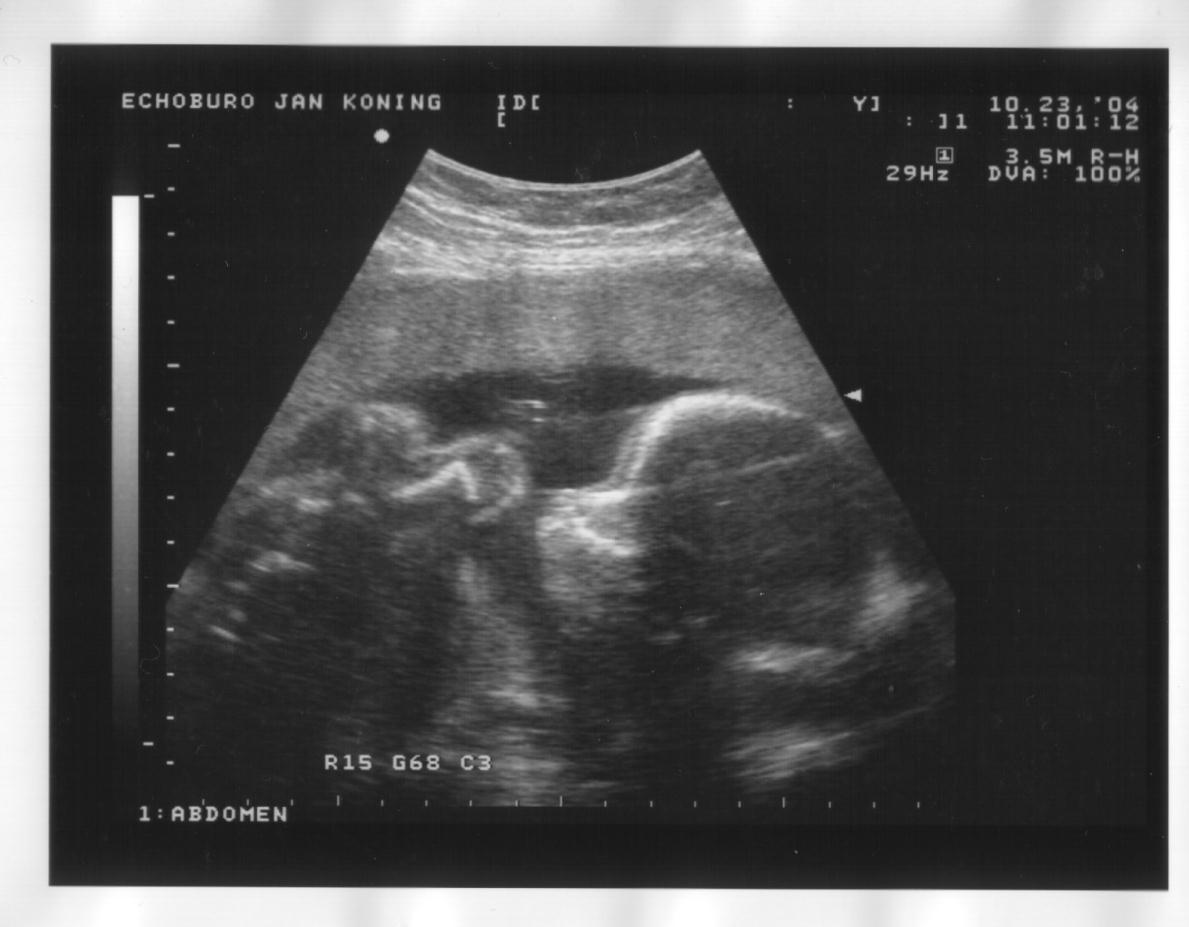

23 oktober 2004

Zijaanzicht hoofd, handje bij het gezicht en oog, bovenste helft borst, opgetrokken knietjes